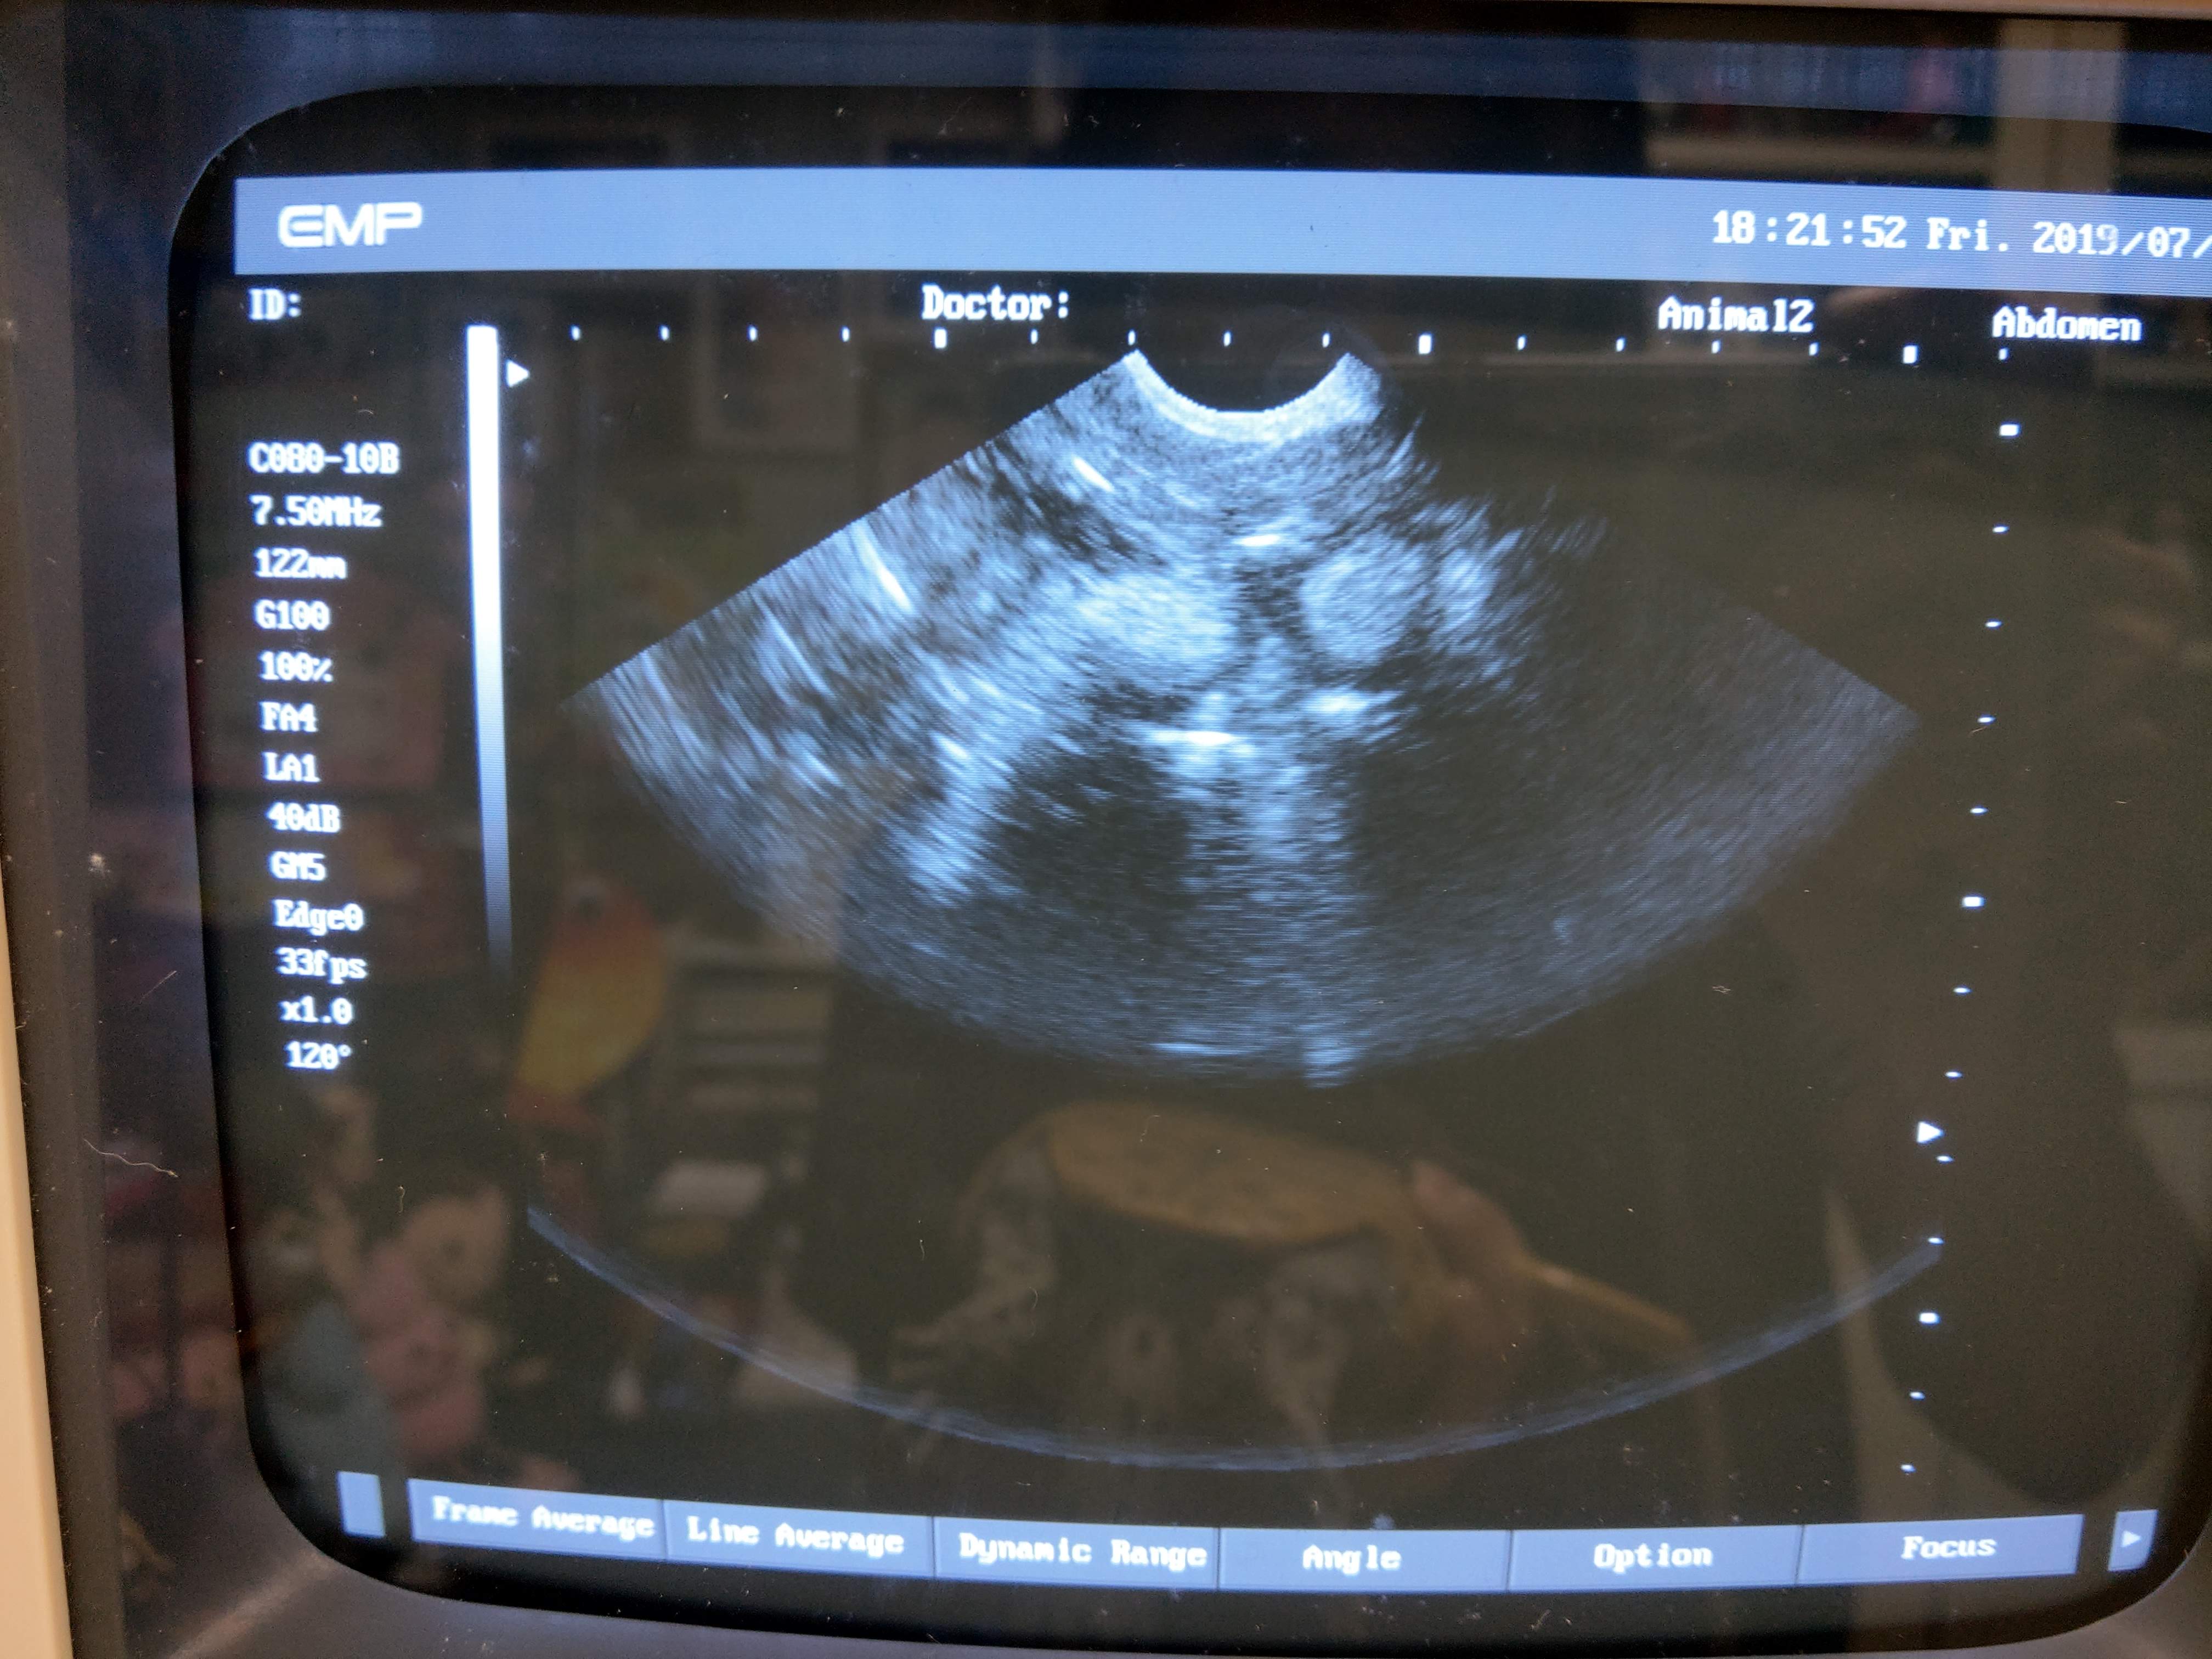

以下是一些記錄照片,有啲圓型冇白邊相信係母龜體內的卵泡,還未完成製蛋過程,還需一段時間才會生蛋。而有白邊的相信是蛋殼的鈣質,體內的蛋已經成熟,隨時準備好產蛋。如果發現有些母龜的蛋在體內己經成熟一段長時間又沒有產下來,就要查證是否有塞蛋等問題。